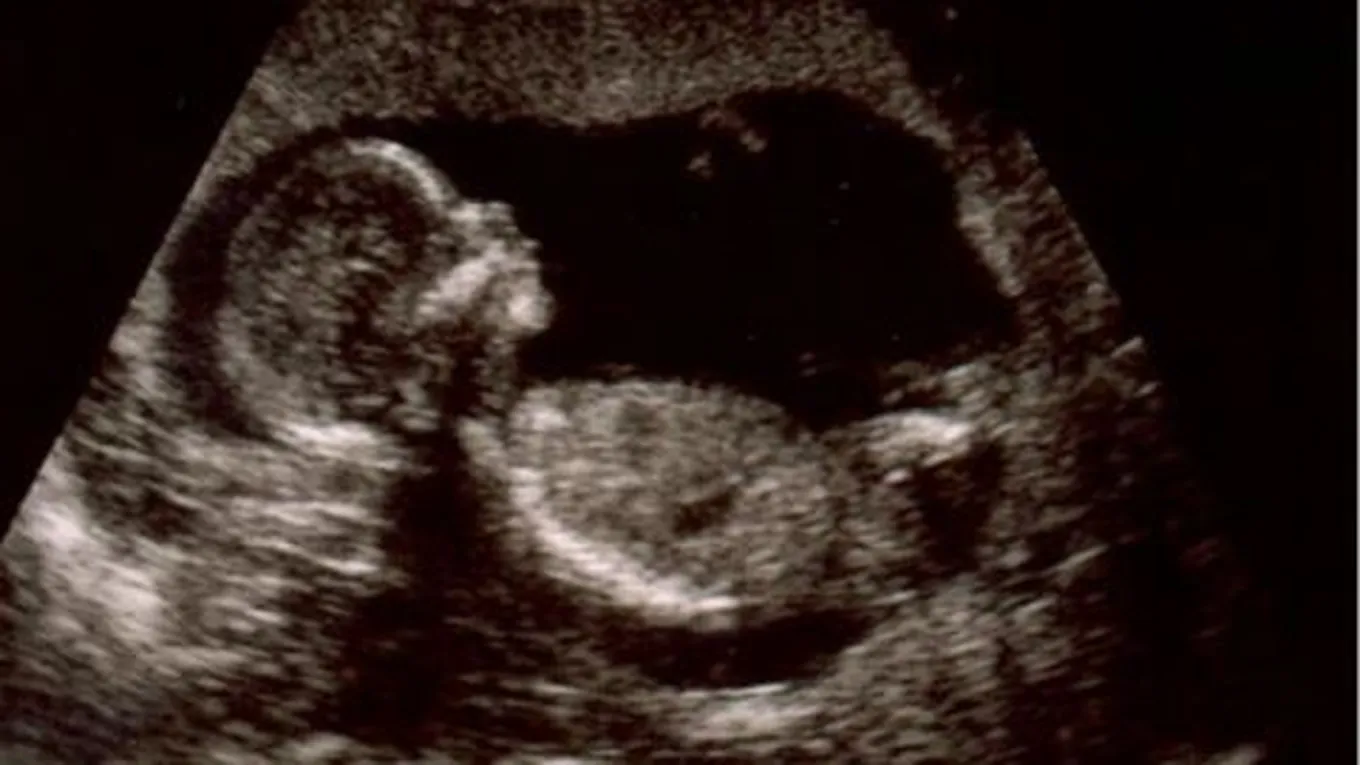

لقد مكننا التصوير فوق الموجات الصوتيّة القدرة على رؤيّة حركات الجنين، فسيبدأ طفلك بالحركة قبل إحساسك بذلك، وستتغيّر حركاته كلّما نما وتطوّر، وإذا كنت محظوظة سيكون طفلك مستيقظاً عند جلسة التصوير وستتمكنين من رؤية حركاته، لكن ما هي هذه الحركات التّي يقوم بها؟: